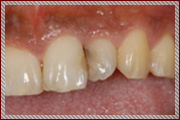

C1〜C2の治療:歯の表面と内側を削って詰める治療を行います

単に虫歯を削って詰めるといっても暗くて小さいお口の中で、

患者さまの健康な歯を傷つけずに虫歯の部分のみを取り除くことは、

非常に困難な作業です。

そのため従来の肉眼による治療では、

虫歯以外の健康な歯もたくさん削られて治療されていました。

その結果、治療後も歯がしみる、痛いなどの不快症状が残ることがあります。

当院では顕微鏡などの拡大鏡を使用することにより、

健康な歯を削らずに残し、

むし歯になってしまった部分だけを取り除いて

そこに接着材料をつかってきれいに封鎖する

MI治療(Minimum Intervention〜最小の侵襲)をおこなっております。

治療後の不快症状を最小限におさえ、なによりも従来の治療よりも歯を削らないため

患者さまの大切な歯を長持ちさせることができます。